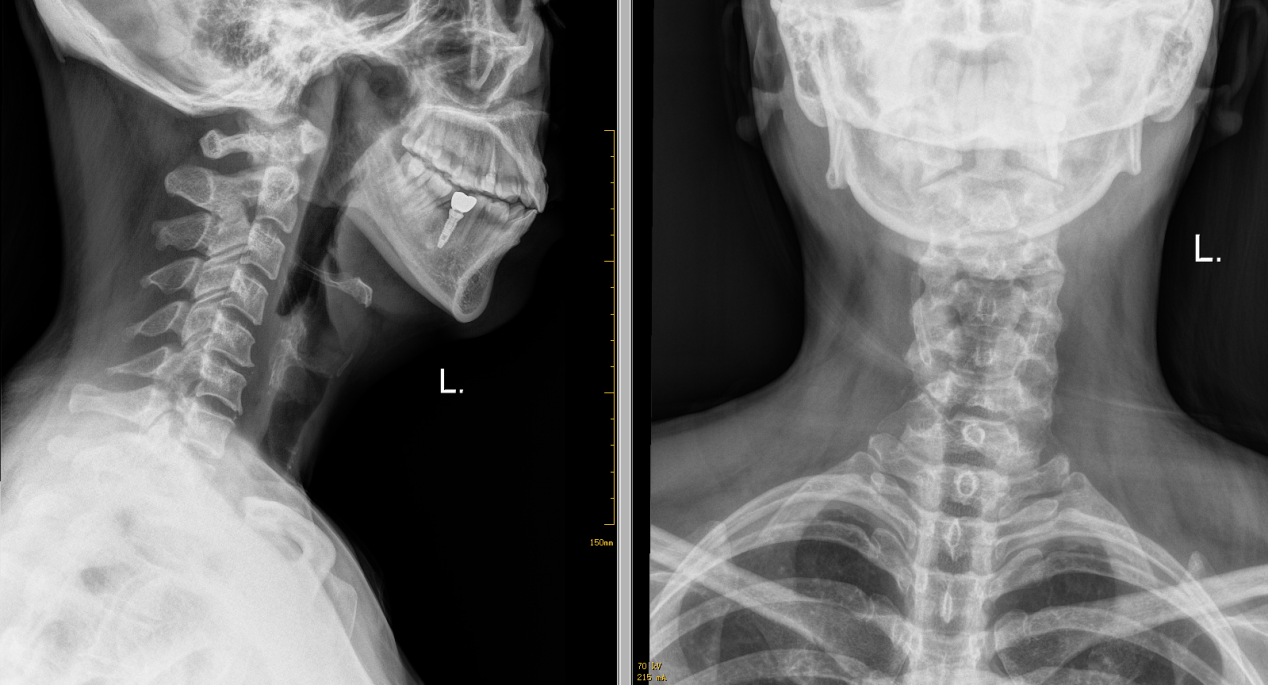

X线检查-正侧位片